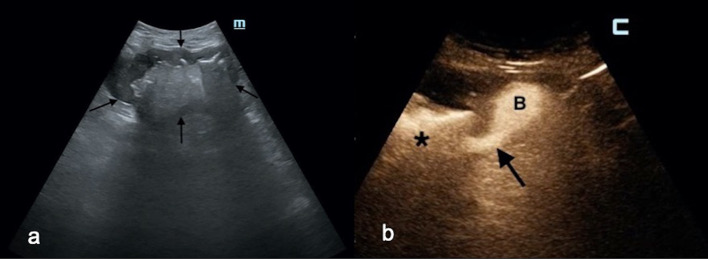

Fig. 4.

a A large liver abscess (between white arrows) was displayed in a 70-year-old woman with malignant obstruction of the common bile duct already treated with endoscopic stenting. b IC-CEUS via the drainage catheter (white arrowheads) demonstrates communication (white arrows) between the abscess cavity (a) and the biliary tree (black star), suggesting obstruction of the biliary endoprosthesis. c In the same patient, another liver abscess (LA) at the dome was drained. The diluted contrast agent solution injected through a catheter (white arrowhead) was seen not only in the liver (black asterisk) but also in the thorax (white arrows), suggesting an extension of the inflammatory process through the diaphragm. d CT scan confirmed IC-CEUS findings and thoracic drainage was carried out

Demonstration of communication with adjacent structures. In one patient, UCA passed from an abdominal abscess into a nearby bowel loop, prompting immediate surgery (Fig. 3). In two PLAs, IC-CEUS showed communication with an apparently unobstructed biliary tree. In this case, not only was the etiology of PLA clarified, but endoscopic stenting was also thereafter programmed. In another patient with malignant obstruction of the common bile duct and two distinct PLAs, IC-CEUS enabled visualization of fistulous communications with the right pleural space and the biliary tree (Fig. 4). Thoracic drainage and replacement of the biliary endoprosthesis were carried out, along with deployment of two catheters to drain the PLAs.